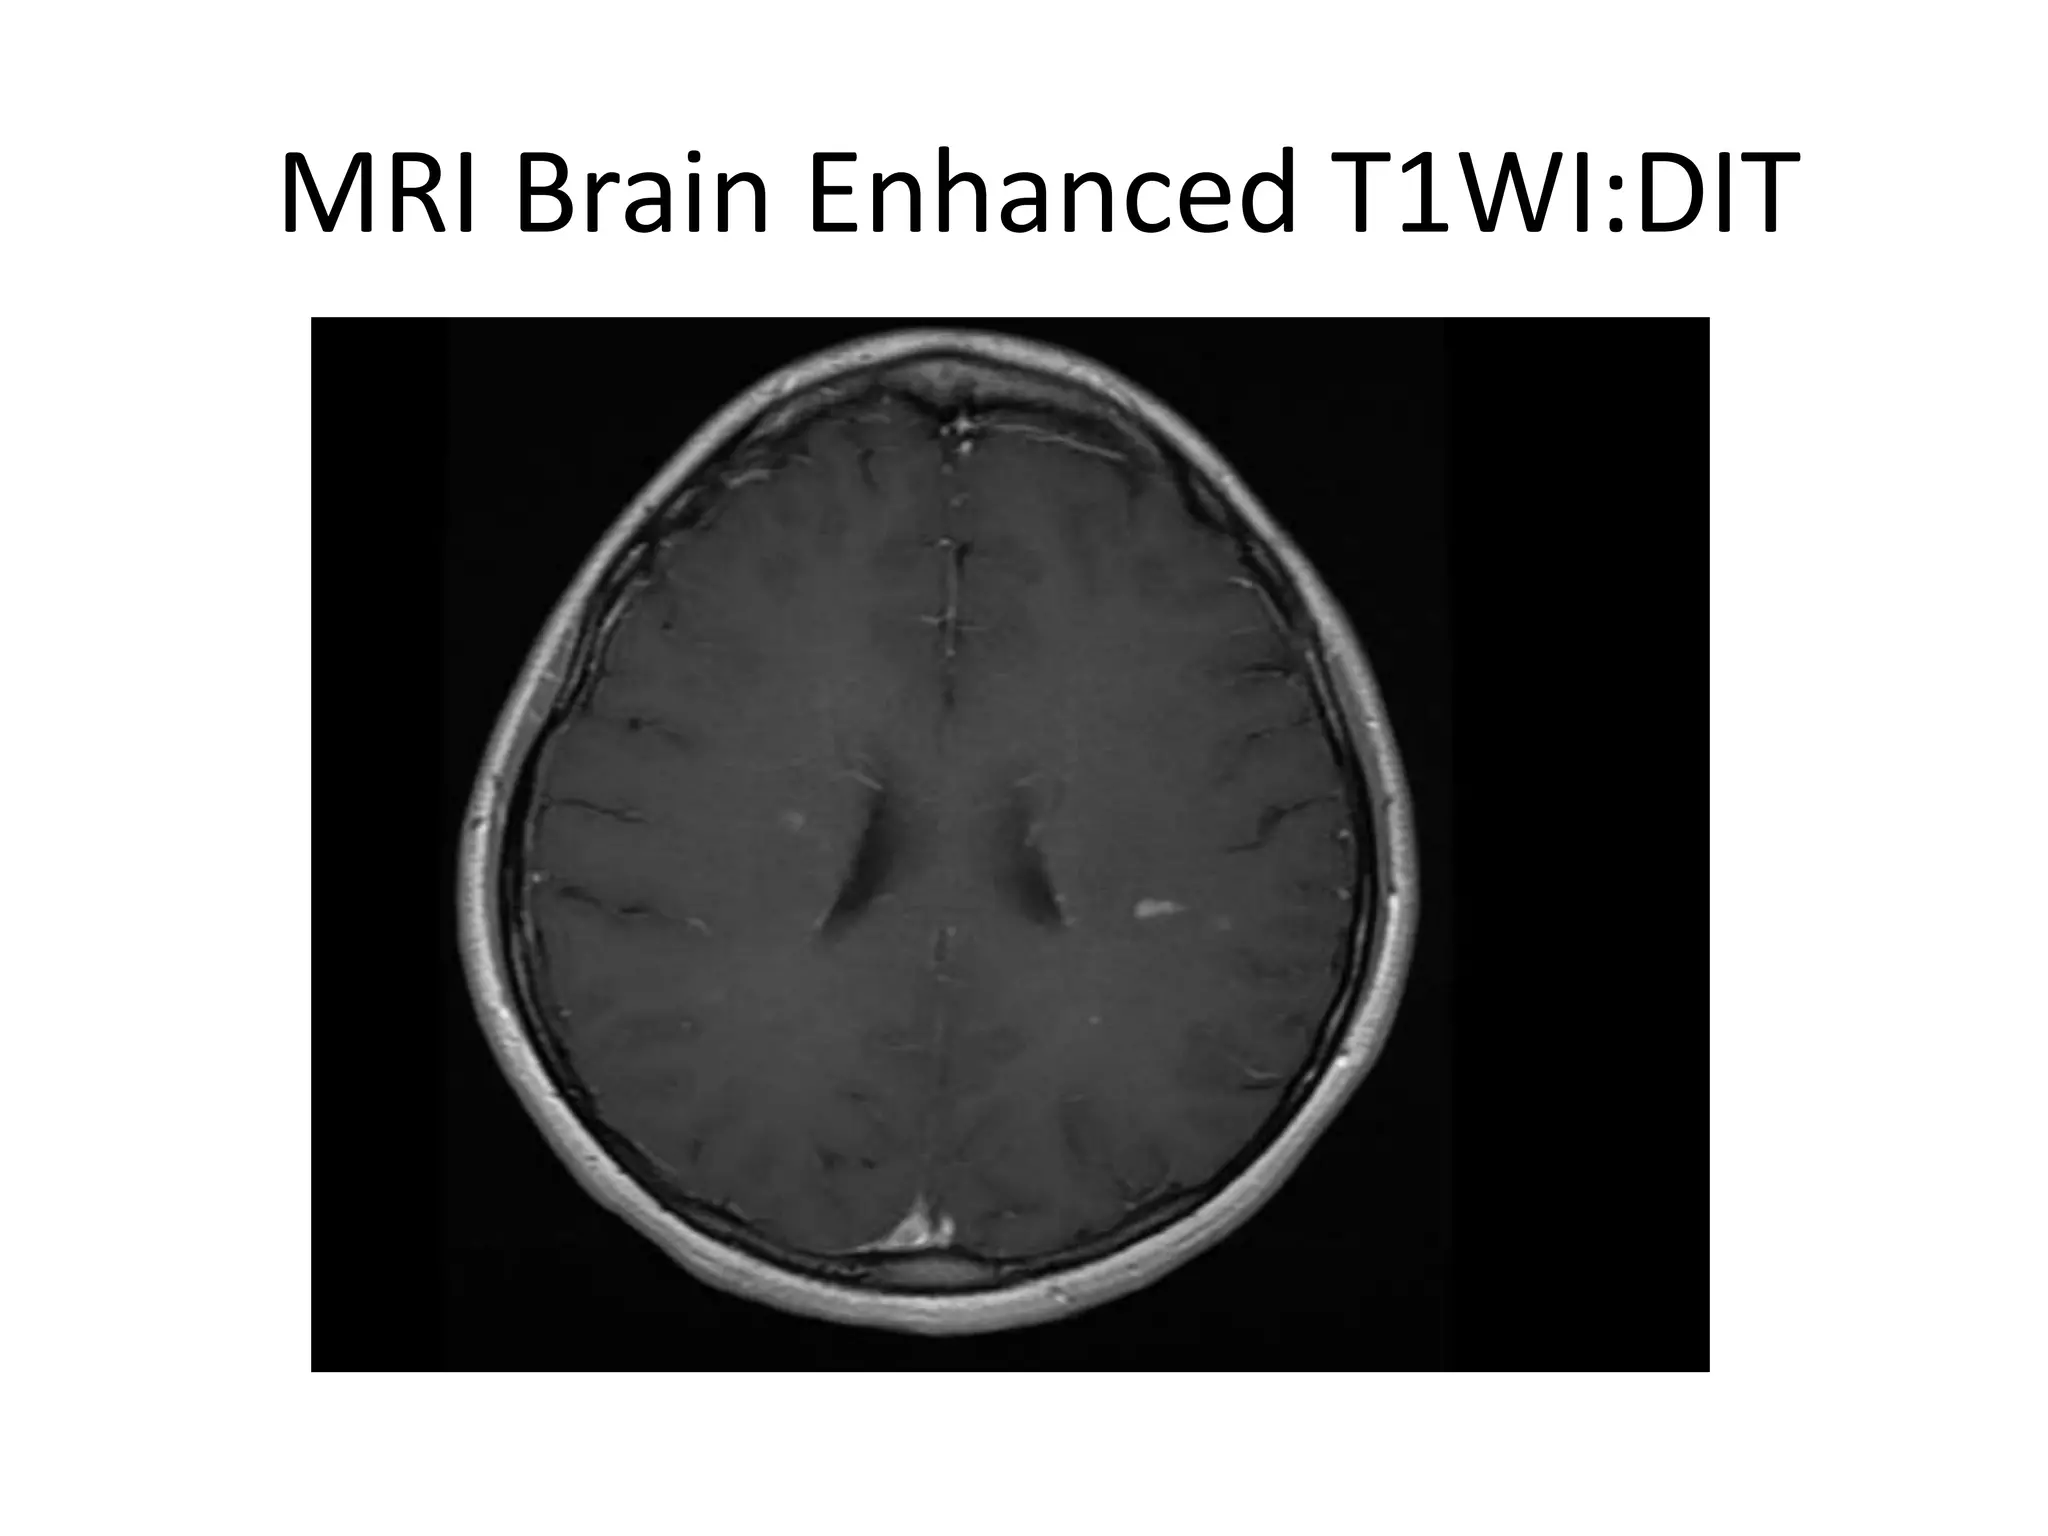

MRI Brain Enhanced T1WI:DIT

Dissemination in Time

Polman CH et al, Ann Neurol 2011; 69:292–302